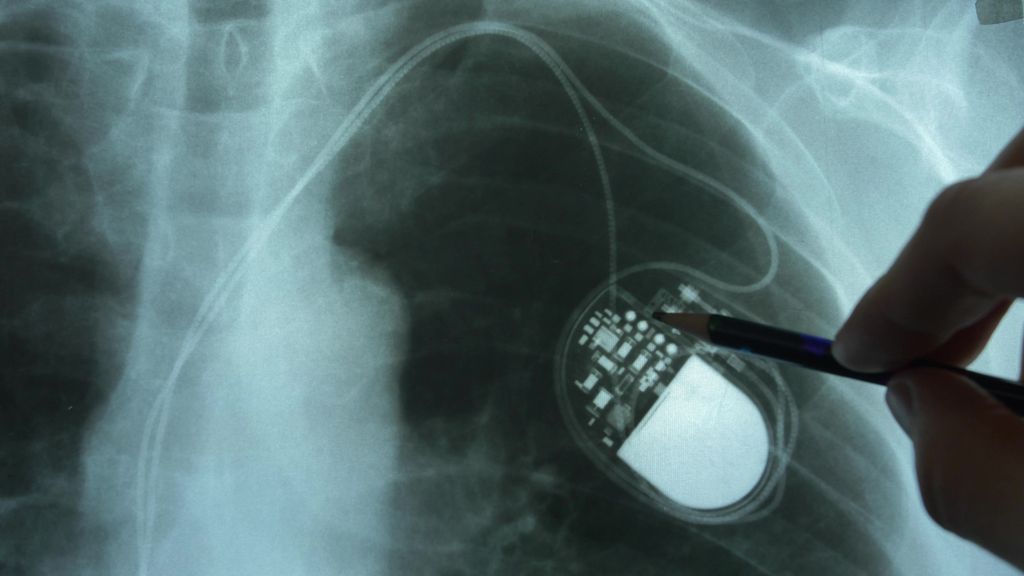

Implantierbare Kardioverter-Defibrillatoren (ICD)

ICD – neue Indikationen und neue Technologien

Seit mehreren Jahrzehnten werden implantierbare Defibrillatoren zur Behandlung von Patient:innen, die ein erhöhtes Risiko für lebensbedrohliche Herzrhythmusstörungen haben, eingesetzt. Das klassische transvenöse System, bestehend aus einem subkutan implantierten Aggregat und einer Hochvoltsonde, die im rechten Ventrikel positioniert wird, oft kombiniert mit einer rechtsatrialen und/oder linksventrikulären Sonde, hat durch ständige Fortschritte ein nahzu ideales Design erreicht. Dieses wurde in einer Arbeit von Mark E. Josephson, Mitbegründer der modernen Elektrophysiologie und kardialen Device-Therapie, bereits vor 30 Jahren beschrieben:1